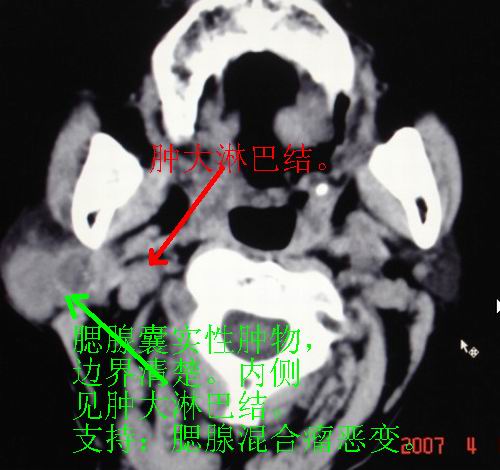

以下是引用zjzjr在2007-4-9 13:27:00的发言:[br]右侧腮腺深浅叶可见一混杂密度区,含有实性及囊性成.考虑右侧腮腺混合瘤,建议ct增强扫描。

以下是引用jiangjing在2007-4-9 15:09:00的发言:[br]考虑右侧腮腺肿瘤[混合瘤可能性大],其他待排[br]建议ct增强扫描。